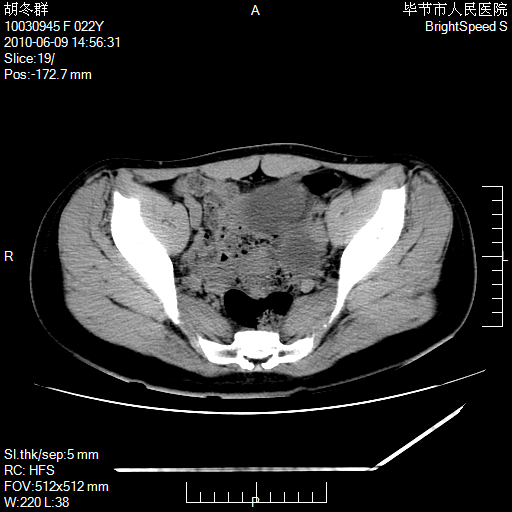

患者23岁,发现腹部包块3月。

左侧卵巢囊腺瘤或囊腺癌

盆腔内囊性占位性病变;考虑左侧卵巢囊腺瘤。

有分隔、壁薄,支持考虑左侧卵巢囊腺瘤。

左侧卵巢浆液性囊腺瘤。

支持考虑左侧卵巢囊腺瘤;宫腔积液。

有分隔、壁薄,支持考虑左侧卵巢囊腺瘤。排尿后,膀胱缩小,由于重力作用,肿块下移就到了膀胱位置,很好理解。